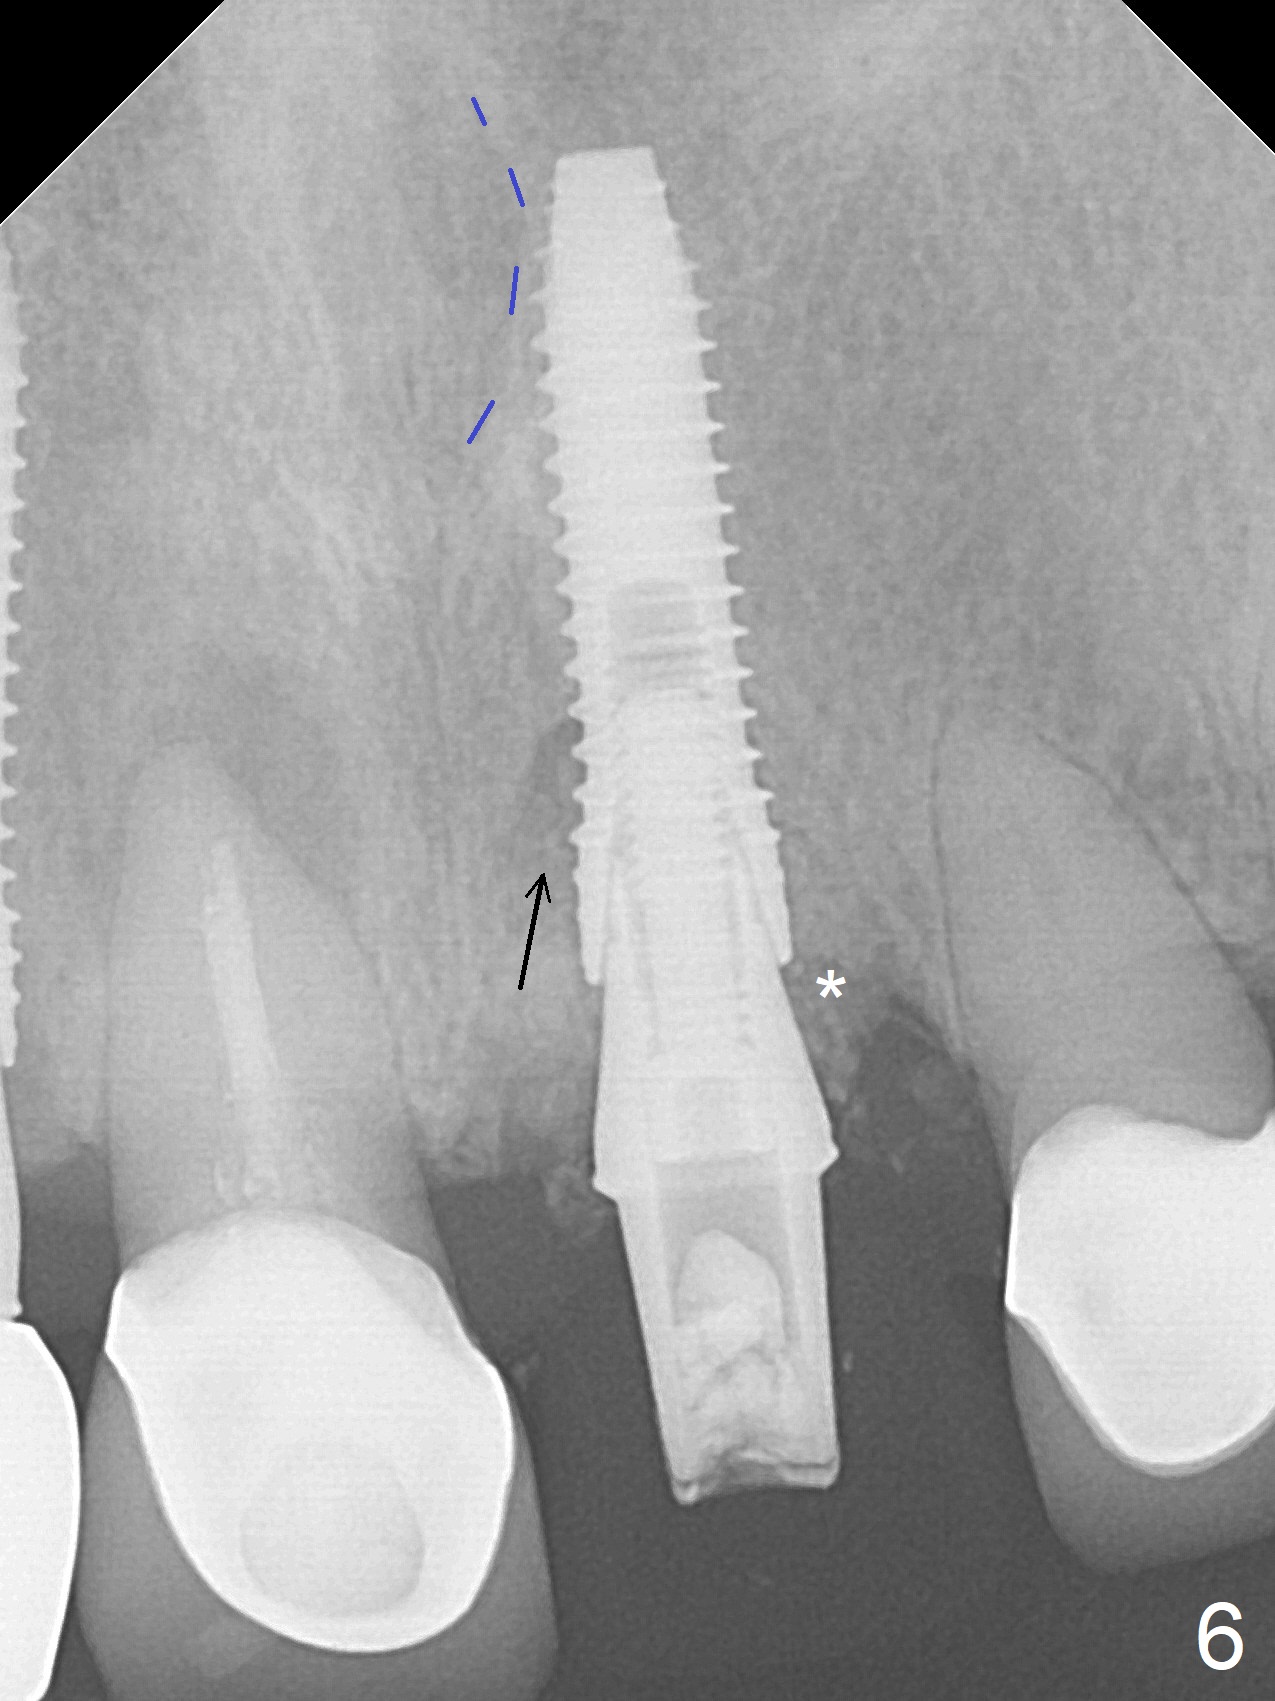

The buccal contour at #9 seems to be slightly concave preop (Fig.1,2 (*)). In fact the buccal plate is found to be lost when the tooth is extracted. Osteotomy is initiated as palatal as possible apical, but the occlusion dictates the coronal end of the osteotomy should be buccal, leaving the buccal gap ~ 2 mm for bone graft. The initial osteotomy (18 mm deep) appears to be close to the Incisive Foramen (Fig.3 blue dashed line). The nasal floor appears to be intact when the drill is removed. Subsequent osteotomy is adjusted so that the apical end of the osteotomy moves distal; when a 3.8x15 mm dummy implant is partially placed, there is clearance (Fig.4). It remains so when a definitive implant is seated (Fig.5); Vanilla graft is placed (Fig.5 *) before placement of a 4.5x5.5(3) mm abutment. More allograft is placed when an immediate provisional is fabricated (Fig.6 arrow and *). The gingiva remains to be recessive 1 month postop (Fig.7). It seems to be related to the bulky gingival margin of the provisional (Fig.8 *). After trimming the latter (Fig.9 *), the gingival margin immediately returns close to normal (Fig.10). The gingival margin is even between #8 and 9 two months postop, but the bone graft is exposed apically (Fig.11 ^). It may heals by itself. Otherwise debridement, regraft, PRF and suture are pending. The coronal portion of the socket heals 4 months postop (Fig.12). The gingival cuff forms by the immediate provisional (which is removed for impression) 4 months postop (Fig.13 *). While the full Zirconia crown at #7 remains intact (Fig.14), the PFM at #9 has porcelain chip (Fig.15). It is partially due to the occlusion; while the crown at #7 has clearance with the opposing dentition (Fig.16 *), the one at #9 has no. The access hole at #9 (Fig.17 *) seems to weaken the crown structure. There is no access hole at #7. No solid posterior support is another contributing factor for chip (Fig.18). The buccal plate has mild atrophy at #7 and 9 (Fig.19 *). A piece of bone graft is being expelled apically at #9 (Fig.20 >) and is removed subsequently (Fig.21). Before impression for repacking porcelain, the opposing incisal edge has been shortened (Fig.22 arrows, as compared to Fig.16). Since the ideal access hole is at the incisal edge (Fig.25 black circle), buccal to the existing one (Fig.24 A), the abutment is torqued before the repaired crown is recemented (Fig.23). Finally the crown has occlusal clearance (Fig.26). Porcelain chips again around the access hole of PFM 1.5 years post 2nd cementation. The dense bone at the crest (*) cannot explain why the abutment is not loose, since it remains incompletely seated (>). As it was trimmed short, an angled abutment is used (Fig.28). The coronal end is lingual, while #9/24 is edge to edge. The lingual aspect of the coronal end of the abutment is heavily trimmed to reduce bulkiness. To prevent chip, Zirconium crown will be fabricated in spite of the fact that it does not match the PFM of #8 (potential shade discrepancy). The patient is pleased with the new Zirconia crown (Fig.29).